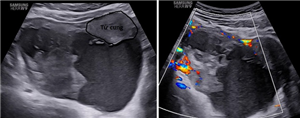

Thai lạc chỗ ở gan (TOG) là một thể không thường gặp của thai trong ổ bụng (TTOB)